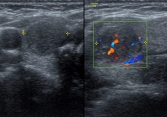

Ung thư tuyến giáp ngày càng trẻ hoá: Bác sĩ chỉ ra những dấu hiệu cần khám ngay nếu không muốn hối hận!

Tỷ lệ ung thư tuyến giáp ở người trẻ ngày càng gia tăng. Việc hiểu,...